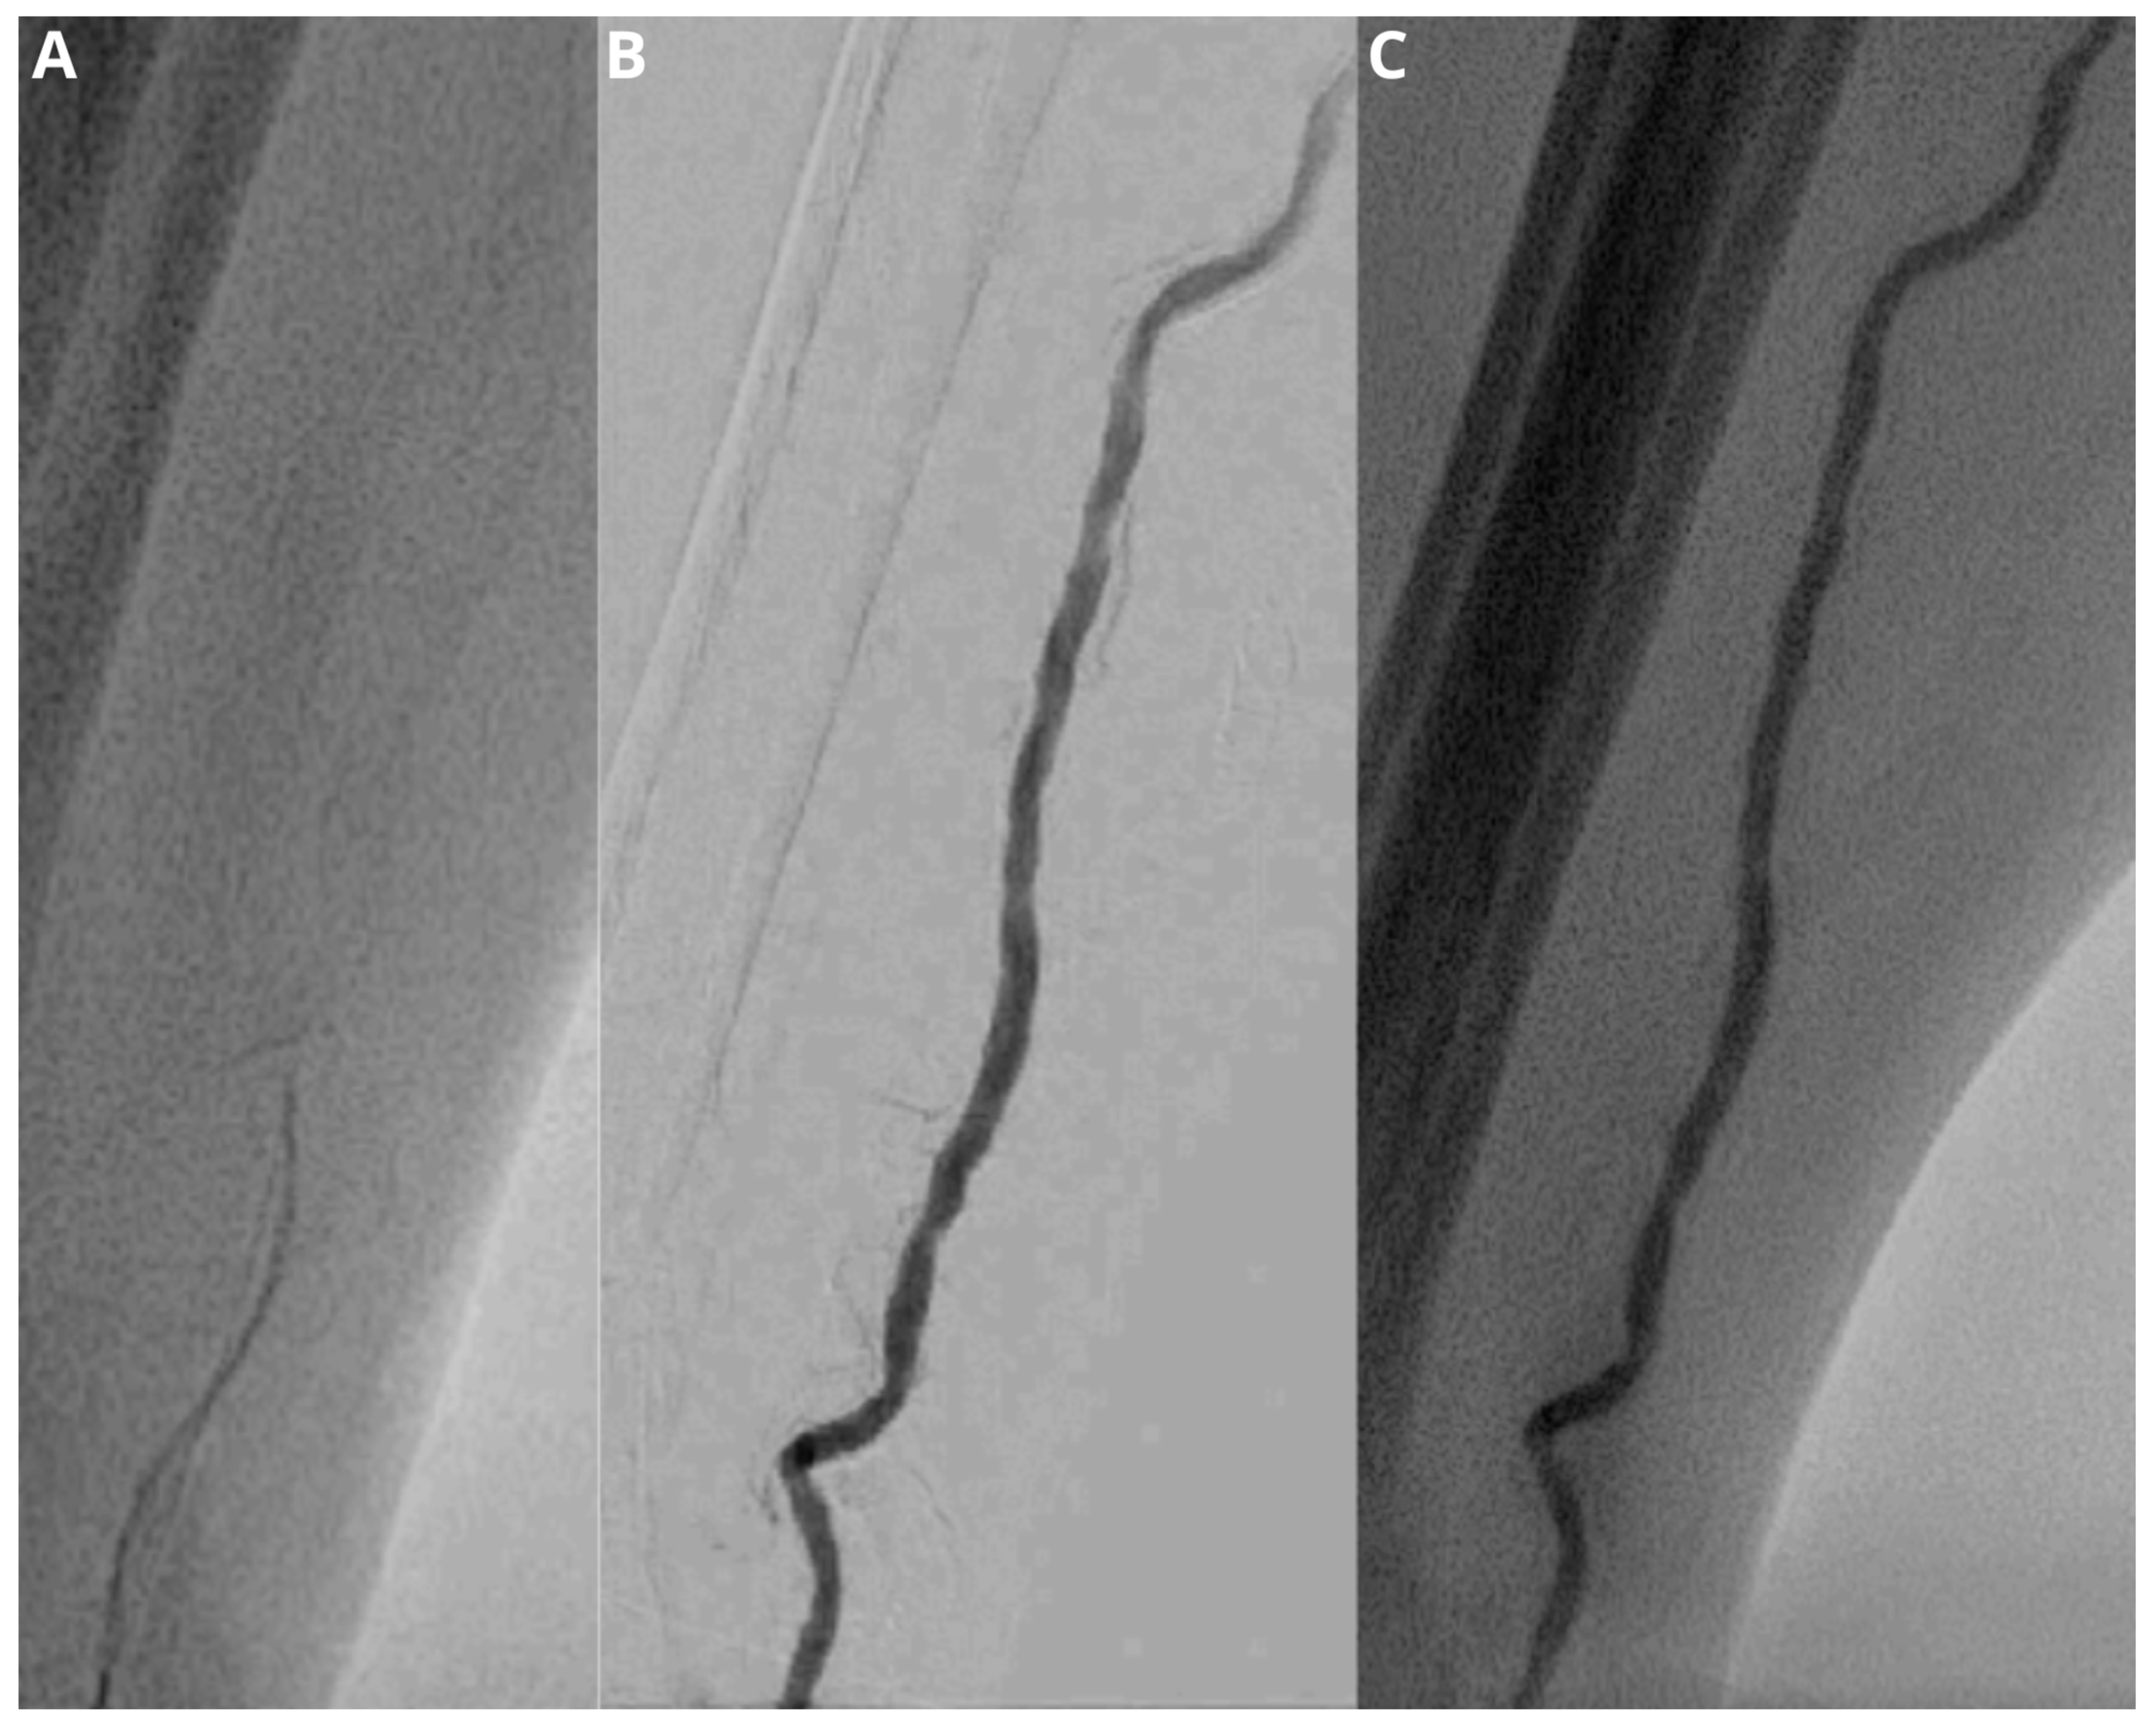

3.2. Procedure Data